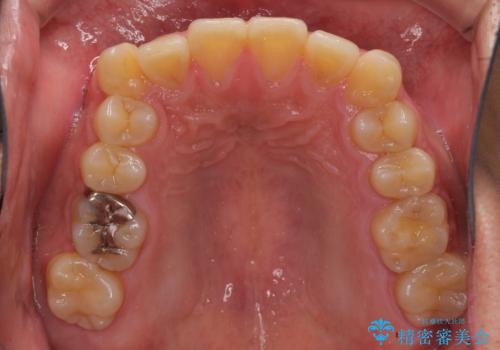

- 前歯のデコボコを気にして来院された患者様です。

配属異動や長時間勤務などによりインビザラインが十分に装着できない期間があり、インビザライン有効期限5年間ギリギリとなってしまいました。

- インビザライン

- 4年8ヶ月